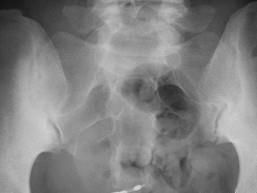

问题 女,45岁,骶髂部疼痛3个月余,请结合影像图像,选择最可能的诊断 ( )

选项 A、骶髂骨骨囊肿 B、骶髂骨骨脓肿 C、骶髂关节结核 D、骶髂关节炎 E、骶髂关节骨折

答案 D